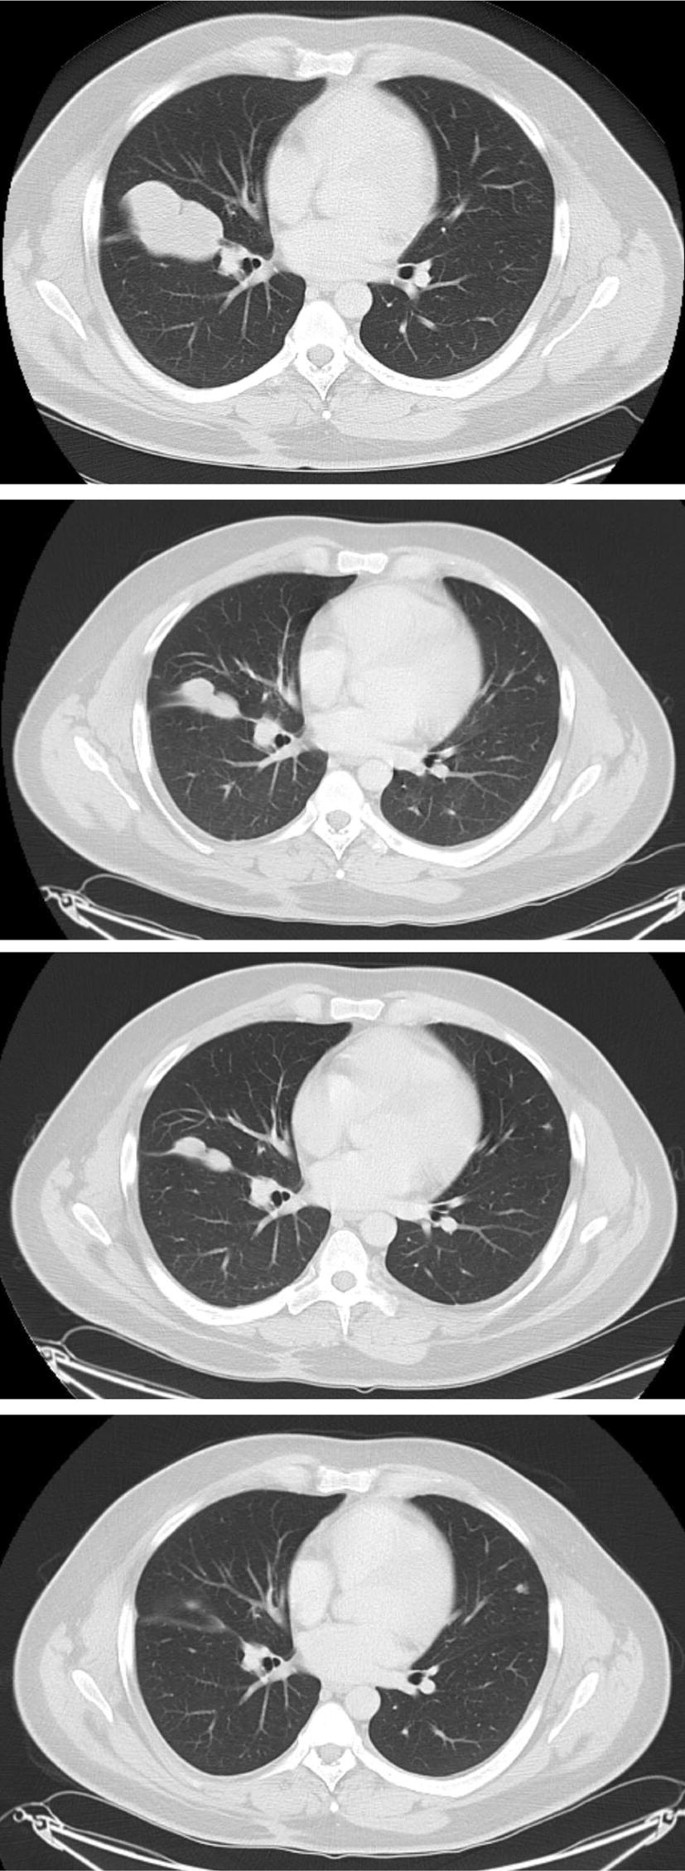

One (11%) patient treated with 6 cycles of doxorubicin had a partial response (PR). The patient was a 33-year-old male with soft tissue myoepithelial carcinoma of the neck. Initial surgery was followed by post-operative radiotherapy. A local recurrence and lung metastases were diagnosed 5.1 months after primary surgery. The patient received first- line palliative chemotherapy with carboplatin and capecitabine, for two cycles, with progressive disease (PD). The patient was offered second-line palliative chemotherapy with doxorubicin (completing 6 cycles), with a PR and a PFS of 8.0 months (see Fig. 1). This patient died of disease 4.1 years after initial diagnosis.

CT images of patient who demonstrated a partial response to chemotherapy. CT thorax baseline prior to doxorubicin chemotherapy demonstrating 6.7 cm metastatic deposit in right thorax, abutting the oblique fissure. CT thorax post two cycles of doxorubicin chemotherapy demonstrating reduction in metastatic deposit in right thorax, abutting the oblique fissure from 6.7 to 4.3 cm. CT thorax post four cycles of doxorubicin chemotherapy demonstrating reduction in metastatic deposit in right thorax, abutting the oblique fissure from 6.7 cm (baseline) to 4.1 cm. 1CT thorax end of treatment (post six cycles) with doxorubicin chemotherapy demonstrating reduction in metastatic deposit in right thorax, abutting the oblique fissure from 6.7 cm (baseline) to 3.5 cm